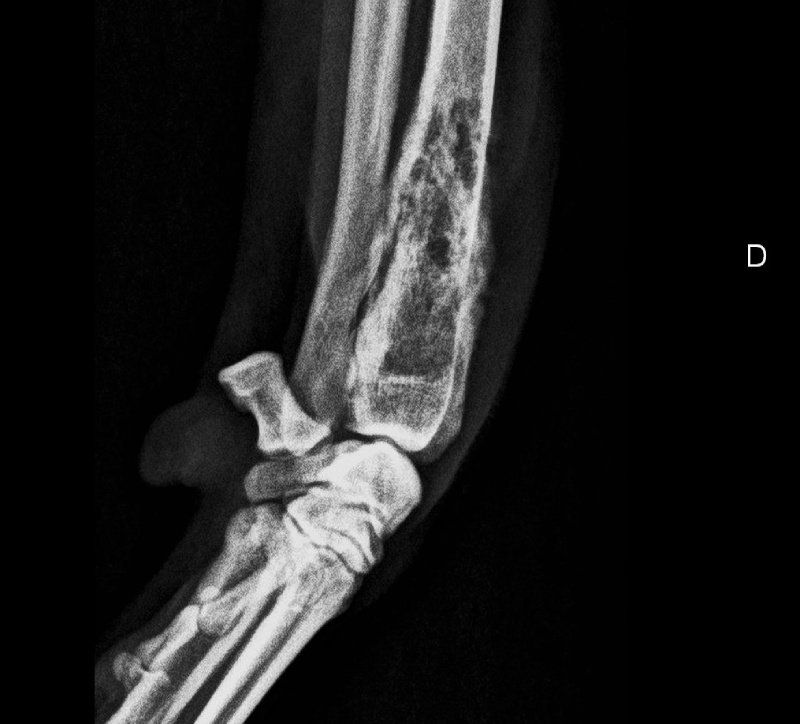

Offriamo i servizi che solo dei veri professionisti seri e qualificati del settore possono assicurare, così che i tuoi amici a quattro zampe possano godere sempre di buona salute. Ci occupiamo anche di eseguire studi radiografici ufficiali per le patologie scheletriche ereditarie, come ad esempio la displasia dell'anca o del gomito.